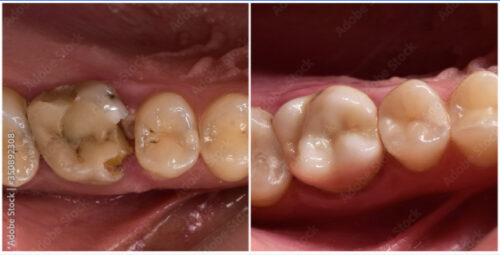

Conservative Dentistry

As its name indicates, it consists of those dental activities aimed at saving the teeth after processes such as caries or periodontitis that compromise their permanence in the mouth. It is essential for the majority of the population due to the high incidence of oral problems.